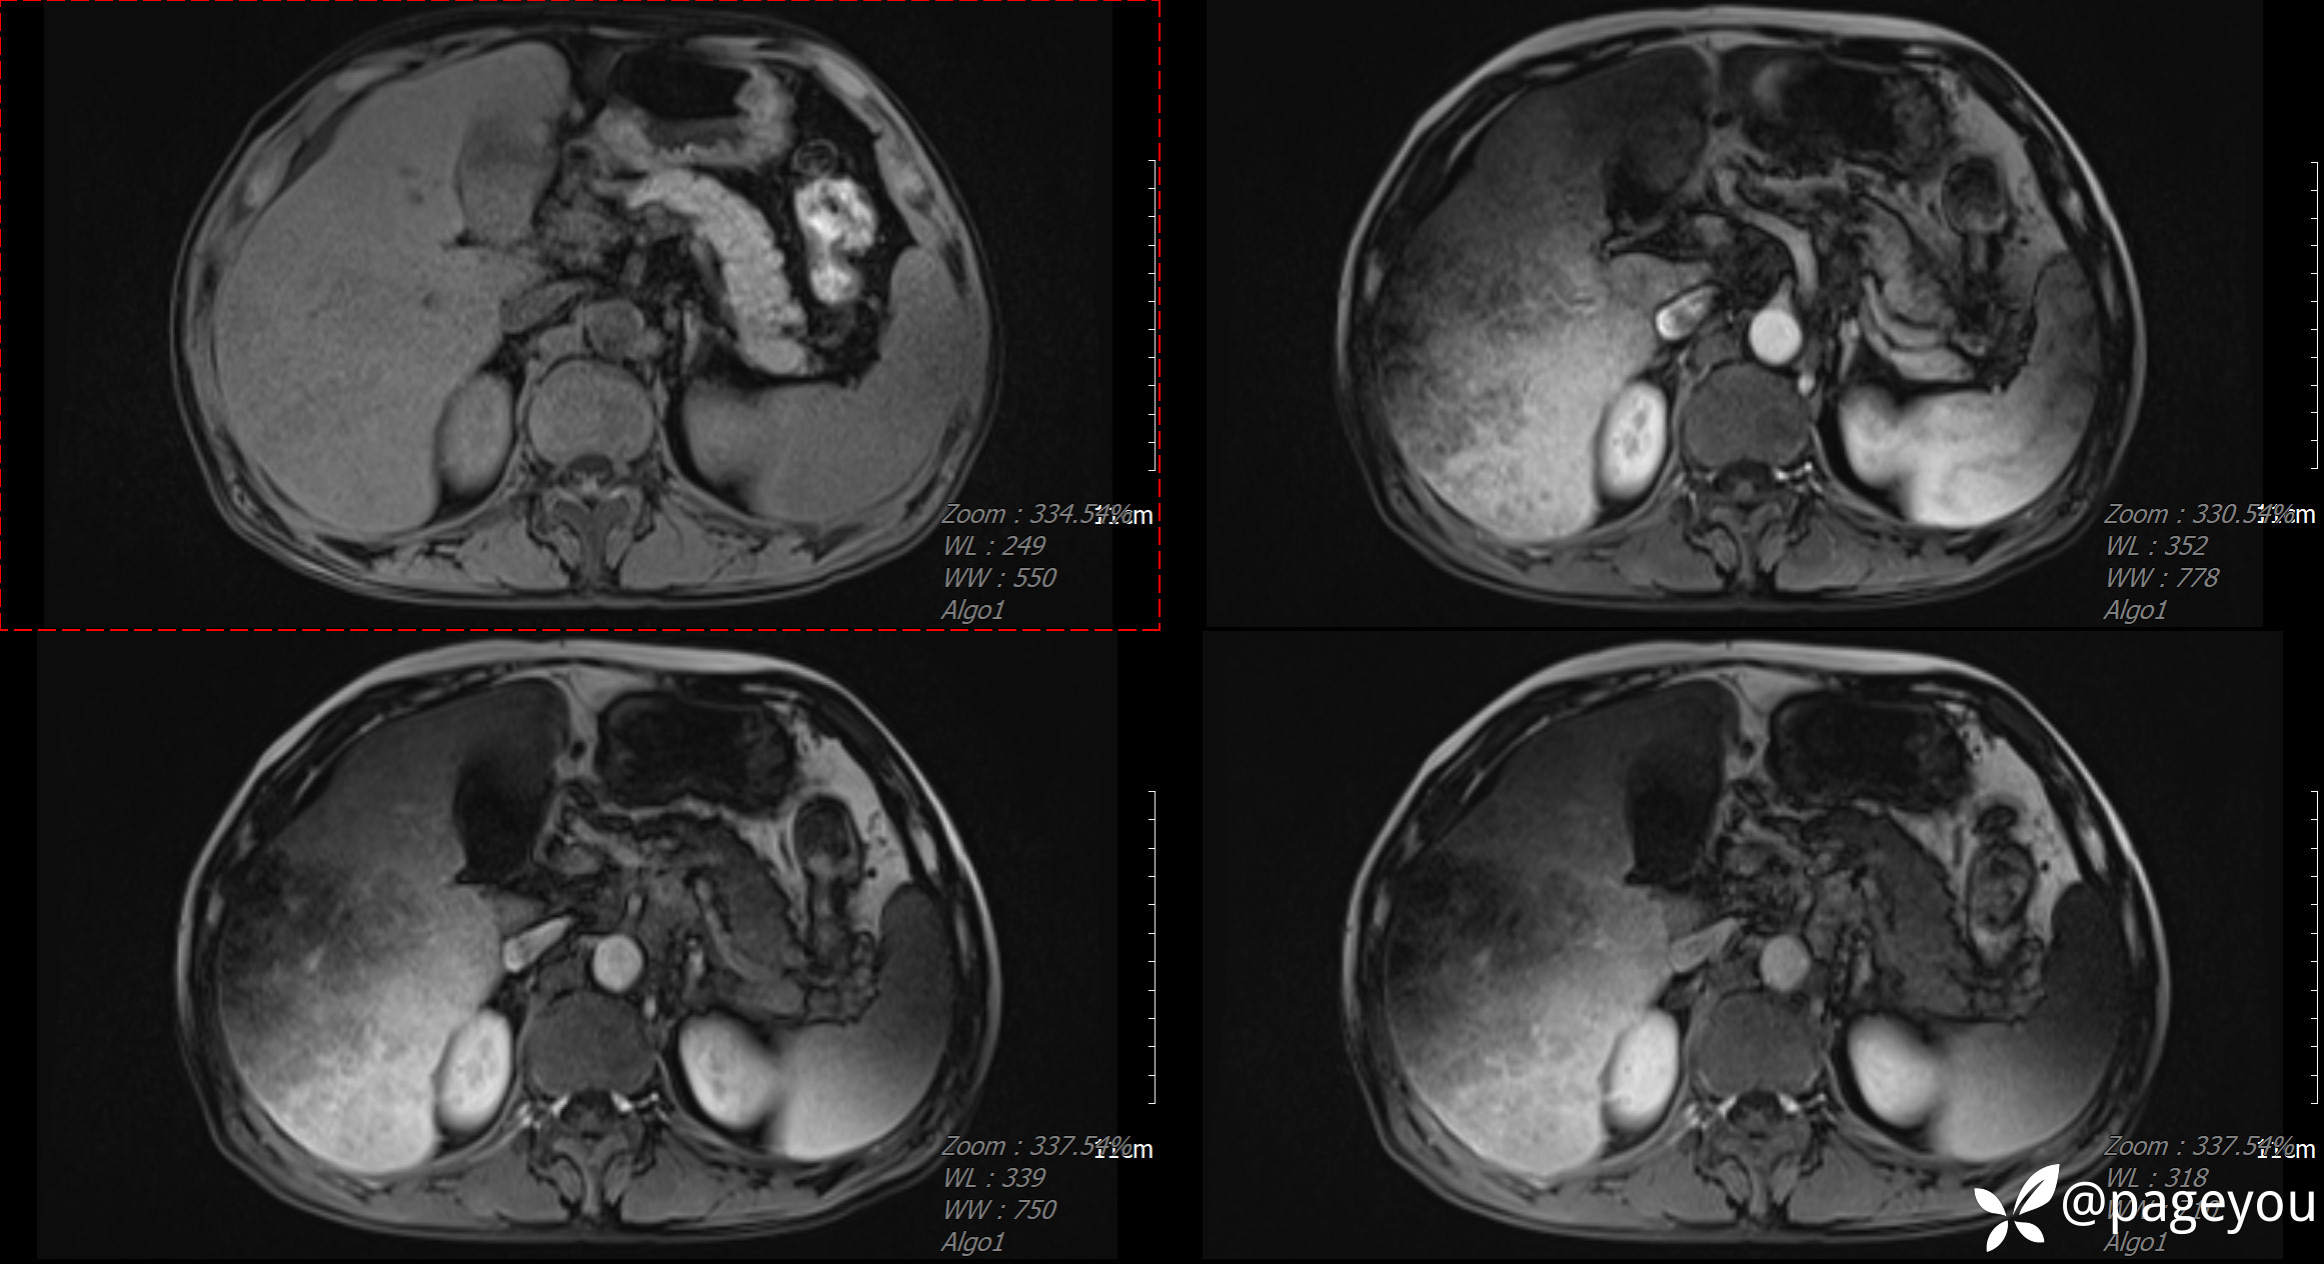

MRI检查: